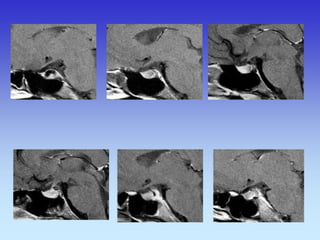

HIPOFIZA

Normalno

Tvorba selarnog područja